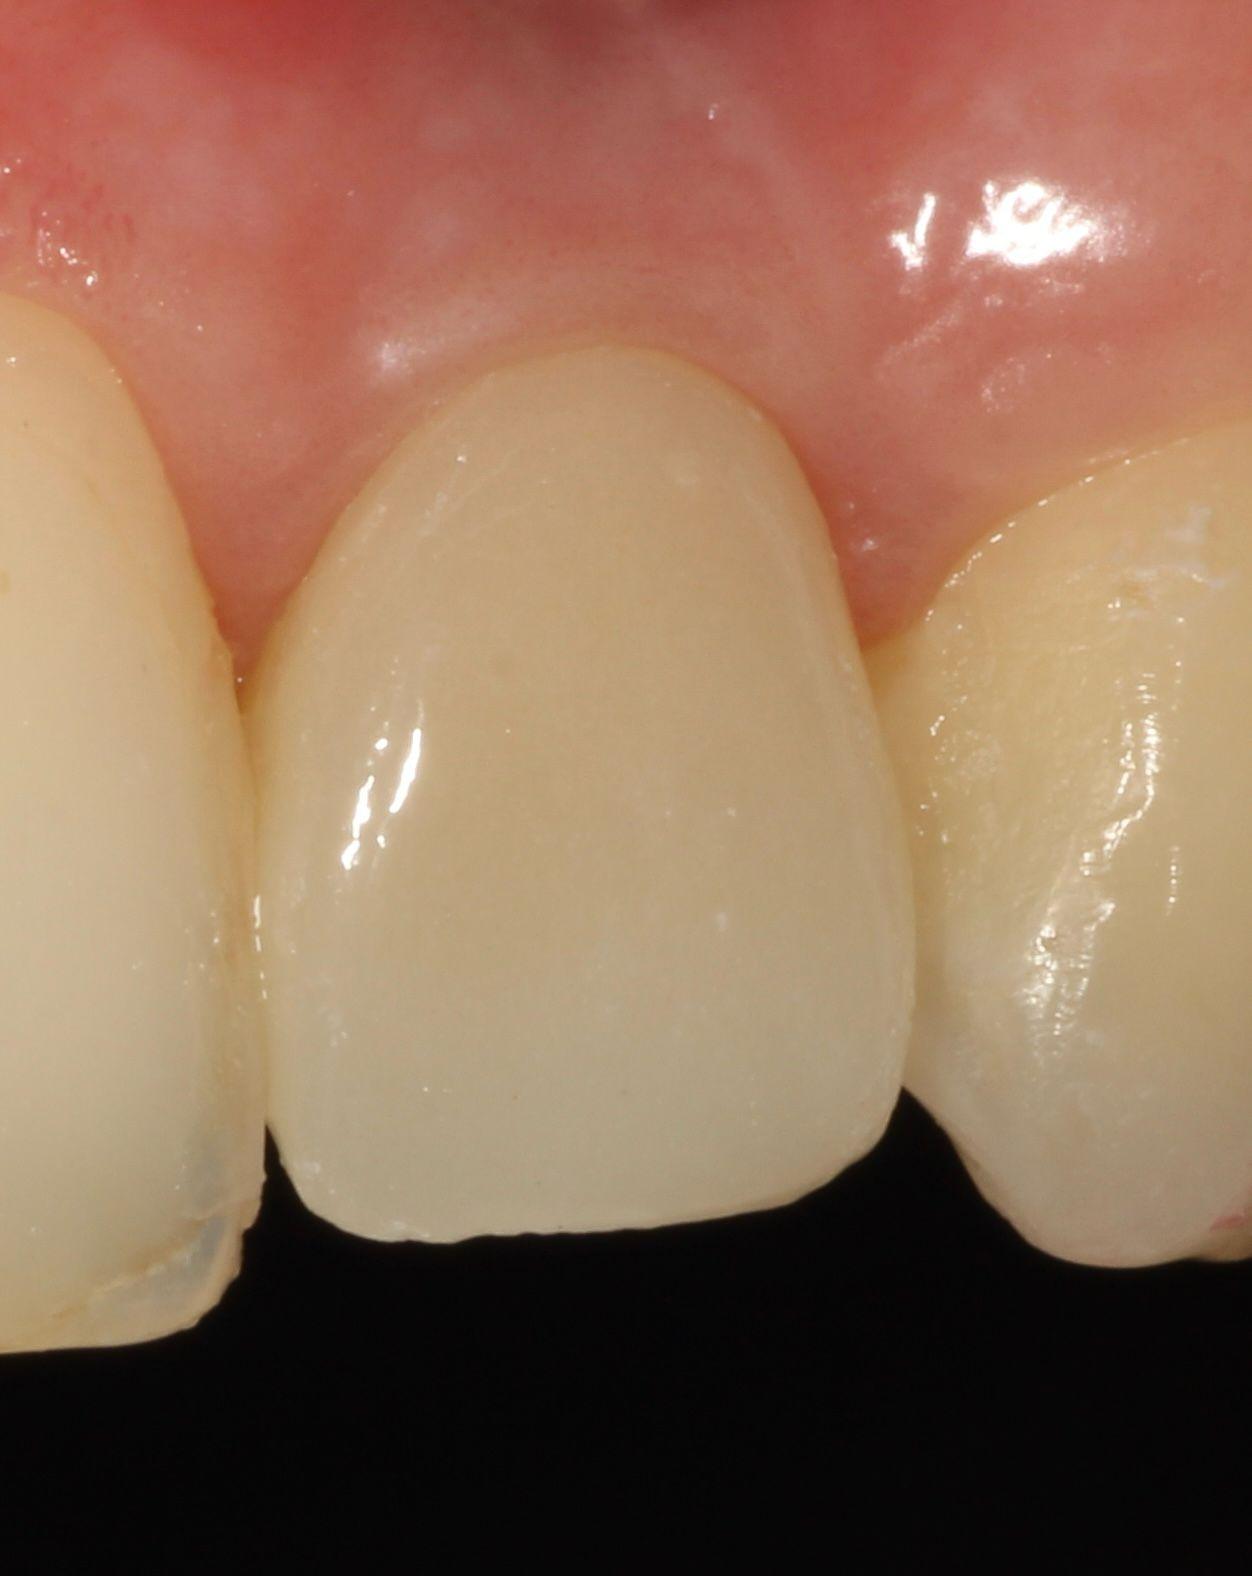

Poprawianie zawsze jest trudne i obarczone dużym ryzykiem niepowodzenia 🙁 Nieumiejętne zarządzanie kością i dziąsłami przy implantacjach skutkuje efektem takim jak na pierwszym zdjęciu. Po przeprowadoznych przez naszego chirurga Michała Mokijewskiego 7 zabiegach korekcyjnych i pomimo znaczącej poprawy, efekt finalny z drugiego zdjęcia jest daleki od naturalnego wyglądu zęba i dziąseł.

Dobrze przeprowadzony zabieg implantacji natychmiastowej daje efekty jak na pozostałych zdjęciach! Na każdym etapie leczenia mamy pełną kontrolę nad wszystkimi aspektami przyszłej odbudowy protetycznej – można powiedzieć, że zachowujemy to, co najtrudneijsze do odtworzenia, czyli kształt dziąseł.

Cytując Michała Mokijewskiego: „Pacjent przychodzi po idealny ząb, a nie po implant”.

Tylko implantacja natychmiastowa pozwala nam uzyskać taki efekt w zaledwie 3 wizyty.